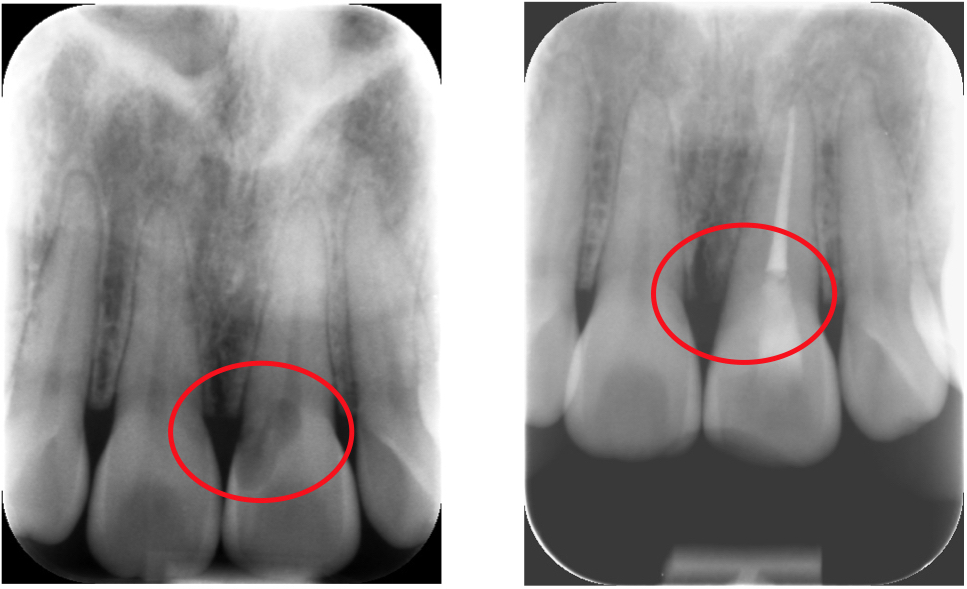

細菌に感染してしまった根管内の神経を

除去します。

細菌が少しでも残ると再発リスクが高まるのでラバーダムを使用して唾液の侵入を防ぎ、殺菌洗浄を行います。

細菌を徹底除去した後、根管に細菌の侵入を防ぐために根管に薬剤を充填します。

流し込んだ薬剤が固まったら歯の内部に細菌が入らないように被せ物を装着して完了です。